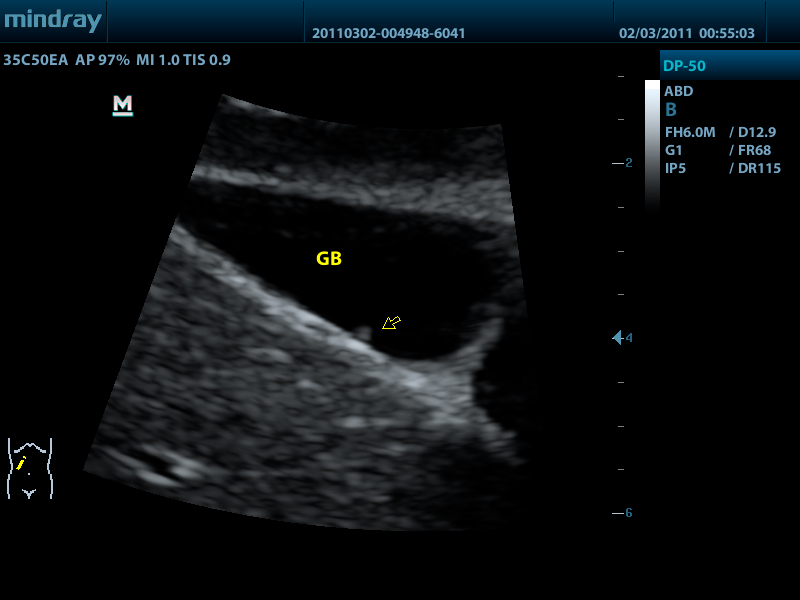

- Конвексный датчик 35C50EA, 1.7 - 6.0 МГц, радиус кривизны 50 мм